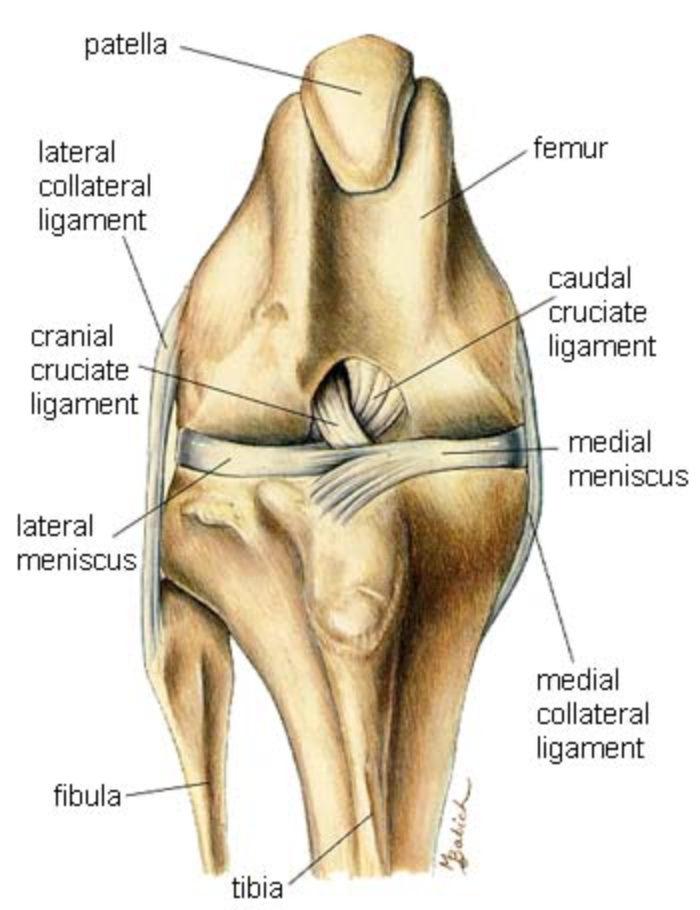

Anatomy of the stifle joint showing the cranial + caudal cruciate ligaments and meniscal cartilages

Cranial cruciate ligament (CrCL) disease is a very common cause of hindlimb lameness in dogs. Partial or complete rupture of the CrCL can occur causing instability of the stifle joint (knee). Injury can cause acute pain and over time leads to chronic degeneration of the joint, cartilage wear, and in some cases meniscal injury (cartilage tear within the joint).